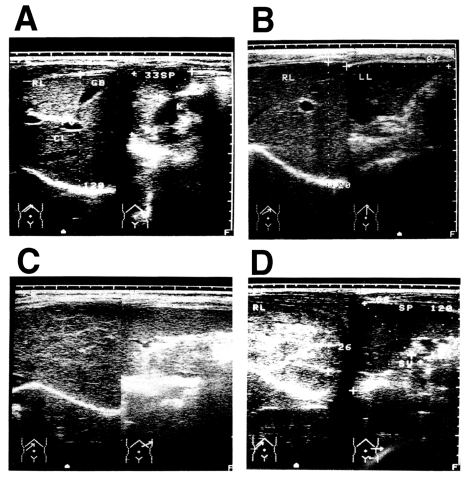

A total of 230 current or former patients with chronic schistosomiasis japonica were examined for liver changes. All patients were from the agricultural village of Beishan, in Yushan county, China, and had their first episode of infection and treatment at least 10 years before this study began. The mean age of the subjects was 52.6 ± 10.5 years and the mean time since their initial treatment was 27.4 ± 8.8 years. Ultrasonographic diagnosis was carried out according to the WHO standard for the diagnosis of liver fibrosis due to schistosomiasis japonica (The Cairo Working Group, 1992; Hatz et al., 1992; Hirayama et al., 1998) (Fig. 1). Ultrasonographic diagnosis determined that there were 44 persons with grade 0 fibrosis, 81 with grade I fibrosis, 99 with grade II fibrosis, and six with grade III fibrosis. The presence of hepatitis B virus (HBV) was not assessed in these patients, but the prevalence of HBV is about 15% in Jiangxi Province (Li et al., 1997). Most of the men in the village smoke tobacco and drink alcoholic beverages, but the women generally do not. The patients had all been treated with praziquantel after each positive faecal examination throughout their lives, but it was not possible to estimate the precise total worm burden of each patient during the clinical course of the disease. Therefore, we tentatively defined an appropriately exposed person as someone with a record of repeated treatments for schistosomiasis japonica over a 10-year period (Hirayama et al., 1998).

Fig. 1

Diagnosis of post-schistosomal liver fibrosis and cirrhosis by ultrasonography. A: Grade 0. B: Grade I. C: Grade II. D: Grade III, showing the fish-scale pattern.

Fig. 1 Diagnosis of post-schistosomal liver fibrosis and cirrhosis by ultrasonography. A: Grade 0. B: Grade I. C: Grade II. D: Grade III, showing the fish-scale pattern.